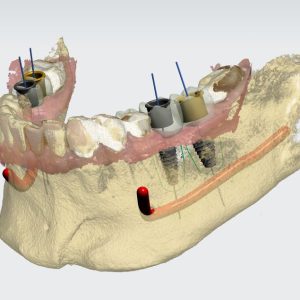

From A to Z Master Hands-On Course for No crestal bone loss